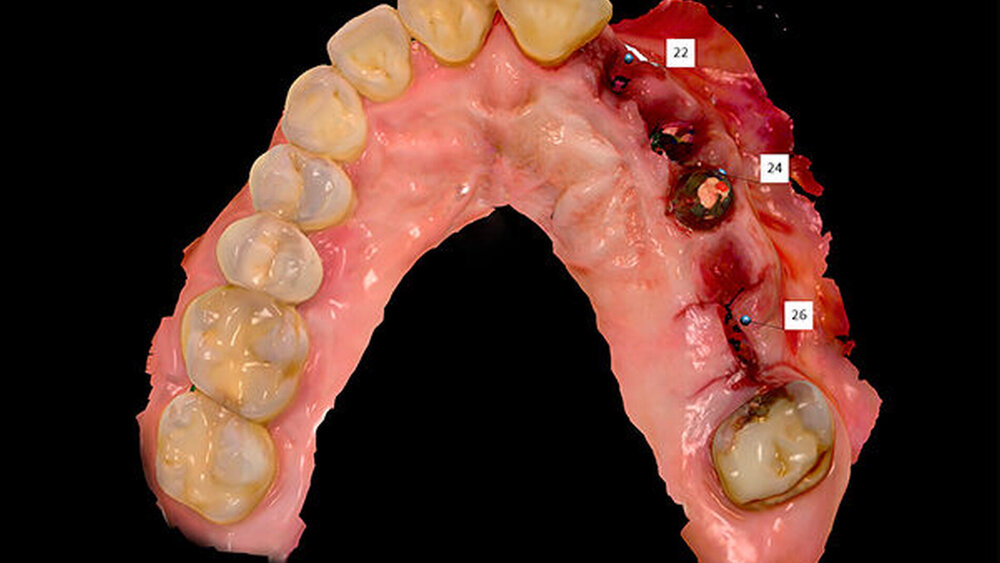

Straumann hat ja schon eine ganze Palette an Zubehörteilen. Wir favorisieren die verschraubte Versorgung. Ein tolles Einsatzgebiet für BLX-Implantate ist aus meiner Sicht auch die All-on-four-Versorgung im Oberkiefer.

Sie meinen Pro Arch-Versorgungen mit BLX?

Schnutenhaus:

Genau, die passenden Abutments gibt es bereits.

Wie gehen Sie vor?

Wir haben extrahiert, dann die Implantate inseriert, direkt nach der Implantation die Scanbodys aufgesetzt, den optischen Abdruck genommen und das Langzeitprovisorium aus PMMA verschraubt. Dass die Innenverbindung immer die gleiche ist, hilft dabei sehr. Eine Prothetik passt tatsächlich auf alle Implantate.